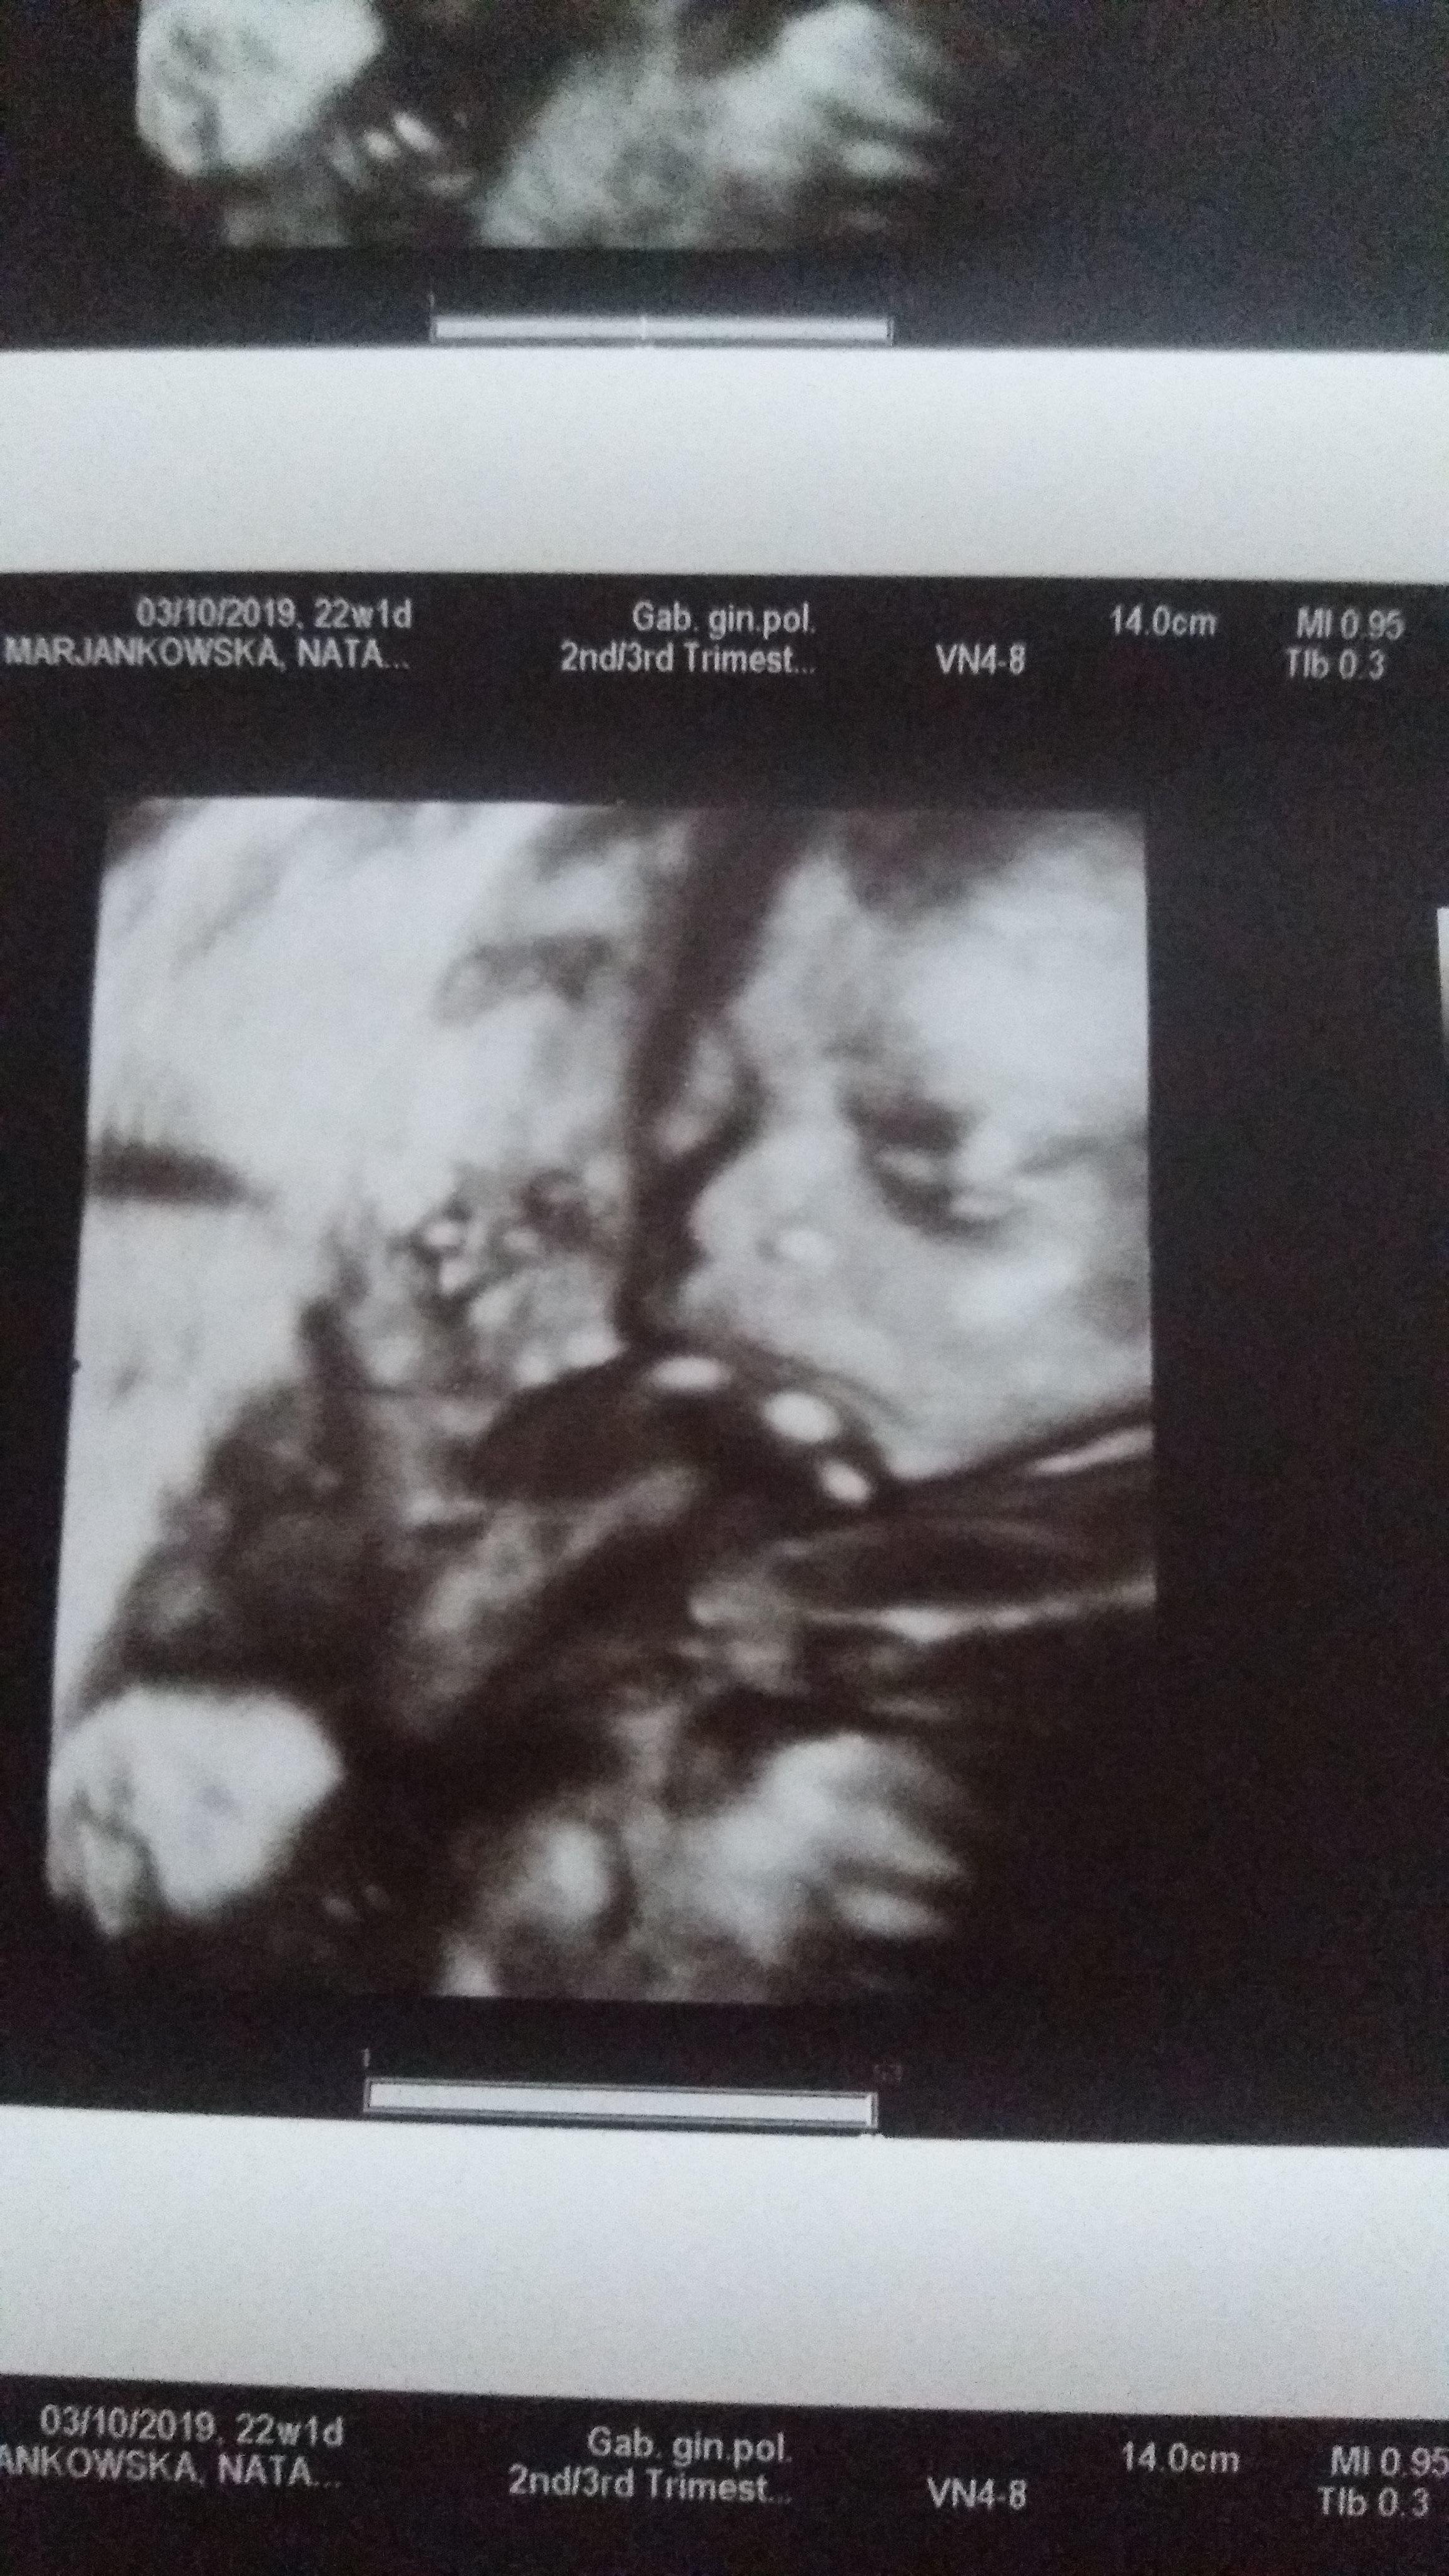

Cześć dziewczyny pozwole sobie opisać moją historię. Syn 9l ciąża idealna. Ponad 2l temu poronienie w 9tc szok ból i niedowierzanie. Po roku zaczęliśmy na nowo starania. Nic nic i nic... w końcu się udało w tym samym mc zaszlam jak w poprzedniej straconej ciąży. Strach ogromny. Szybko więc zapisałam się do gin. Nie zdążyłam pójść na pierwszą wizyte, kiedy dostałam brązowych plamien w 5tc. Trafiłam do szpitala.... beta ok pęcherzyk był i tyle.... miałam czekać..... wszystko było ok do 11 tc ogromne krwawienie rano w toalecie. Czułam, ze to koniec krew była wszędzie. Pojechałam na izbę przyjęć.... po ok 3h zrobiono mi usg dziecko żyło skąd krwawienie nie wiadomo..... na drugi dzień rano jeszcze gorszy koszmar . Znowu krew i ogromne coś galaretkowate ze mnie wyleciało. Bylo wielości pięści... teraz to juz koniec na pewno.... załamałam się po 3h przyszedł łaskawie lekarz.... usg i dziecko żyje ale był to ogromny krwiak i odklejająca się kosmowka. Lekarze byli sceptyczni...... nikt nie dawał nadziei. Dostałam duphaston i l4. Po5 dniach wyszlam ze szpitala. Moja gin na wizycie powiedziała, że z kosmowką ok a krwiak się zmniejszył..... nie trwalo to długo w 16 tc znowu krwawienie znowu szpital znowu leki znowu krwiaki blisko kosmówki. Znowu lekarze patrzyli na mnie jak na dziwadło..... brałam duphaston znowu i nospę i przetrwałam . Od 20 tc jest wszystko ok. Zero krwiaków usg połówkowe super . Aktualnie 24+ 3 z om a z 25+3 z usg. Więc dziewczyny krew nie musi oznaczać straty ciąży. Trzymam za wszystkie kciuki.

Załączniki

• IMG-20200306-WA0012.jpeg

IMG-20200306-WA0012.jpeg

1,3 MB · Wyświetleń: 59